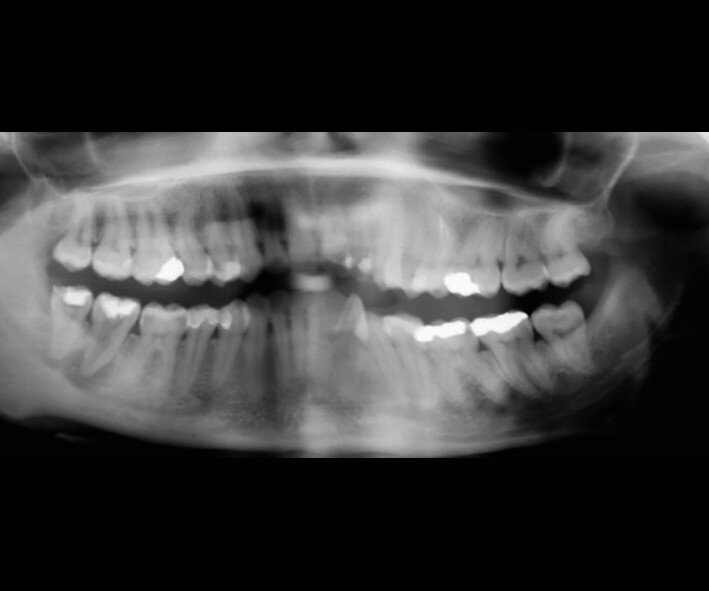

Fig. 15a: Radiograph: Pre-op panoramic.

Fig. 18a: Radiographs: Pre-op panoramic.

The left mandibular second molar of a 35-year-old female patient had been compromised because of a vertical root fracture and a large periapical lesion was present. After explanation and informed consent, the treatment was scheduled. The right mandibular third molar was preferred as a donor to the left mandibular third molar because of a more compatible anatomy and for an easier stabilisation. After local anaesthesia of both the donor and the recipient sites with 2 per cent mepivacaine with 1:100,000 adrenaline, the left mandibular second molar was extracted and the alveolus debrided. Then the donor tooth was atraumatically extracted, quickly repositioned in the recipient site and stabilised with sutures at about 1.5–2.0 mm of infraocclusion. An antibiotic (amoxicillin/clavulanic acid, 1 g, by mouth twice a day for five days) and a non-steroidal anti-inflammatory drug (ibuprofen, 600 mg, by mouth twice a day for five days) were prescribed, along with rinses with 0.2 per cent chlorhexidine. The sutures were removed after two weeks and endodontic treatment was performed after three months. The periapical lesion healed and the tooth was fully functional after 12 years (Figs. 14a–d & 15a–d).

A 23-year-old female patient presented with a vertical root fracture of tooth #47. Tooth #48 was transplanted to site #47. The tooth was fully functional after eight years (Figs. 17a–d & 18a–d).